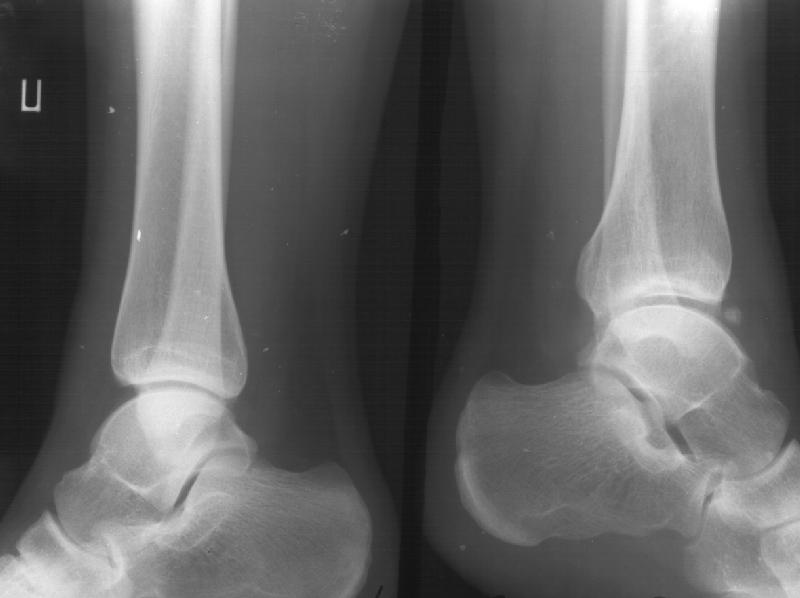

Девочка 14 лет полтора года назад оперирована в детской больнице по поводу спирального перелома костей голени (снимок 1)- выполнен закрытый остеосинтез стержнем Богданова, введенным ретроградно с медиальной стороны (снимок 2). Фиксатор после сращения удален

(см. снимки 3 и 4, после удаления, для сравнения со здоровой стороной, фас - стоя с нагрузкой на обе ноги). В настоящее время беспокоят боль и отеки в области голеностопного сустава при нагрузках, после ходьбы. В покое и ночью боли нет.Амплитуда движений в голеностопном суставе практически полная. Имеется заметная боковая нестабильность, т.е. несостоятельность дельтовидной связки и межберцоого синдесмоза. Складывается впечатление, что при остеосинтезе был отколот и смещен в сторону сустава костный фрагмент позади внутренней лодыжки, увеличилось смещение отломка заднего края, что привело к столь ранним проявлениям деформирующего артроза. Встает вопрос - что делать сейчас?Артодез - наверно, рано. Ревизию сустава, моделирующую резекцию?Пластику связок? Что-то еще? Заранее спасибо.

умаю дельтовидная связка и дистальный тибио-фибулярный синдесмоз не повреждены. При операции гвоздь вколочен внутрь сустава между медиальным

малеолярным отростком и талюсом так, что отломил и оттеснил медиально ту часть медиального маллеола, который обеспечивает медиальную стенку "ворот" (мортис) голеностопа. Сейчас при ходьбе талюс сублюксирует в медиальном

направлении. От этого боли и отёки при ходьбе.